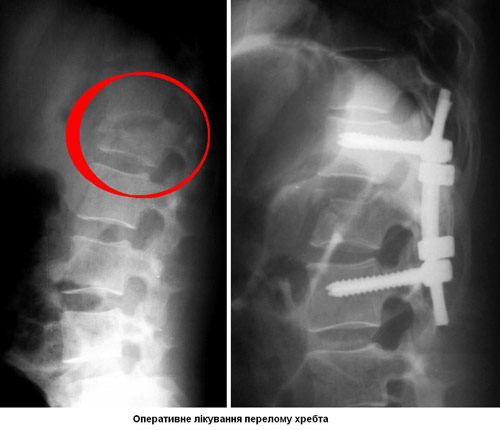

- Операція. Часто необхідно проведення термінової операції, щоб видалити фрагменти кісток, сторонні тіла, грижу міжхребцевого диска або зламані фрагменти хребця, що здавлюють вміст хребетного каналу. Операція також може знадобитися для стабілізації хребта, щоб запобігти появі болю або деформації. Існують деякі протиріччя щодо кращого часу проведення операції. Деякі хірурги вважають, що її необхідно виконувати раніше, інші вважають, що безпечніше почекати кілька днів до проведення будь-якої операції. Науково обгрунтованих доказів переваг ранніх (ургентних) операцій не отримано.

Зусилля нейрохірургів при лікуванні травм спинного мозку не мають вирішального впливу на прогноз патології. Навіть найбільш важкі операції з використанням найсучаснішого обладнання не завжди відновлюють втрачені функції. Зазвичай лікування дає позитивні результати, але діапазон може бути широким: від суб'єктивного поліпшення до повноцінного одужання. Операції підлягають 50% хворих, іншим доводиться лікуватися консервативно.

Мета операції - стабілізація хребта металевими конструкціями (імплантантами). Наша клініка була першою в СНД, яка застосувала сучасні конструкції при переломах хребта. Нині ми використовуємо імпортні конструкції типу CD Horison Legacy (США), Atlantis (США), Sextant (США), Socore (Франція). Операції вимагають складної рентгенівської техніки та спеціального інструментарію. При неускладнених переломах хребта хворі можуть ходити після таких операцій уже на другий - третій день. Також в Міжнародному центрі нейрохіургіі вперше в Україні впроваджено метод мініінвазивних операцій при переломах хребта.